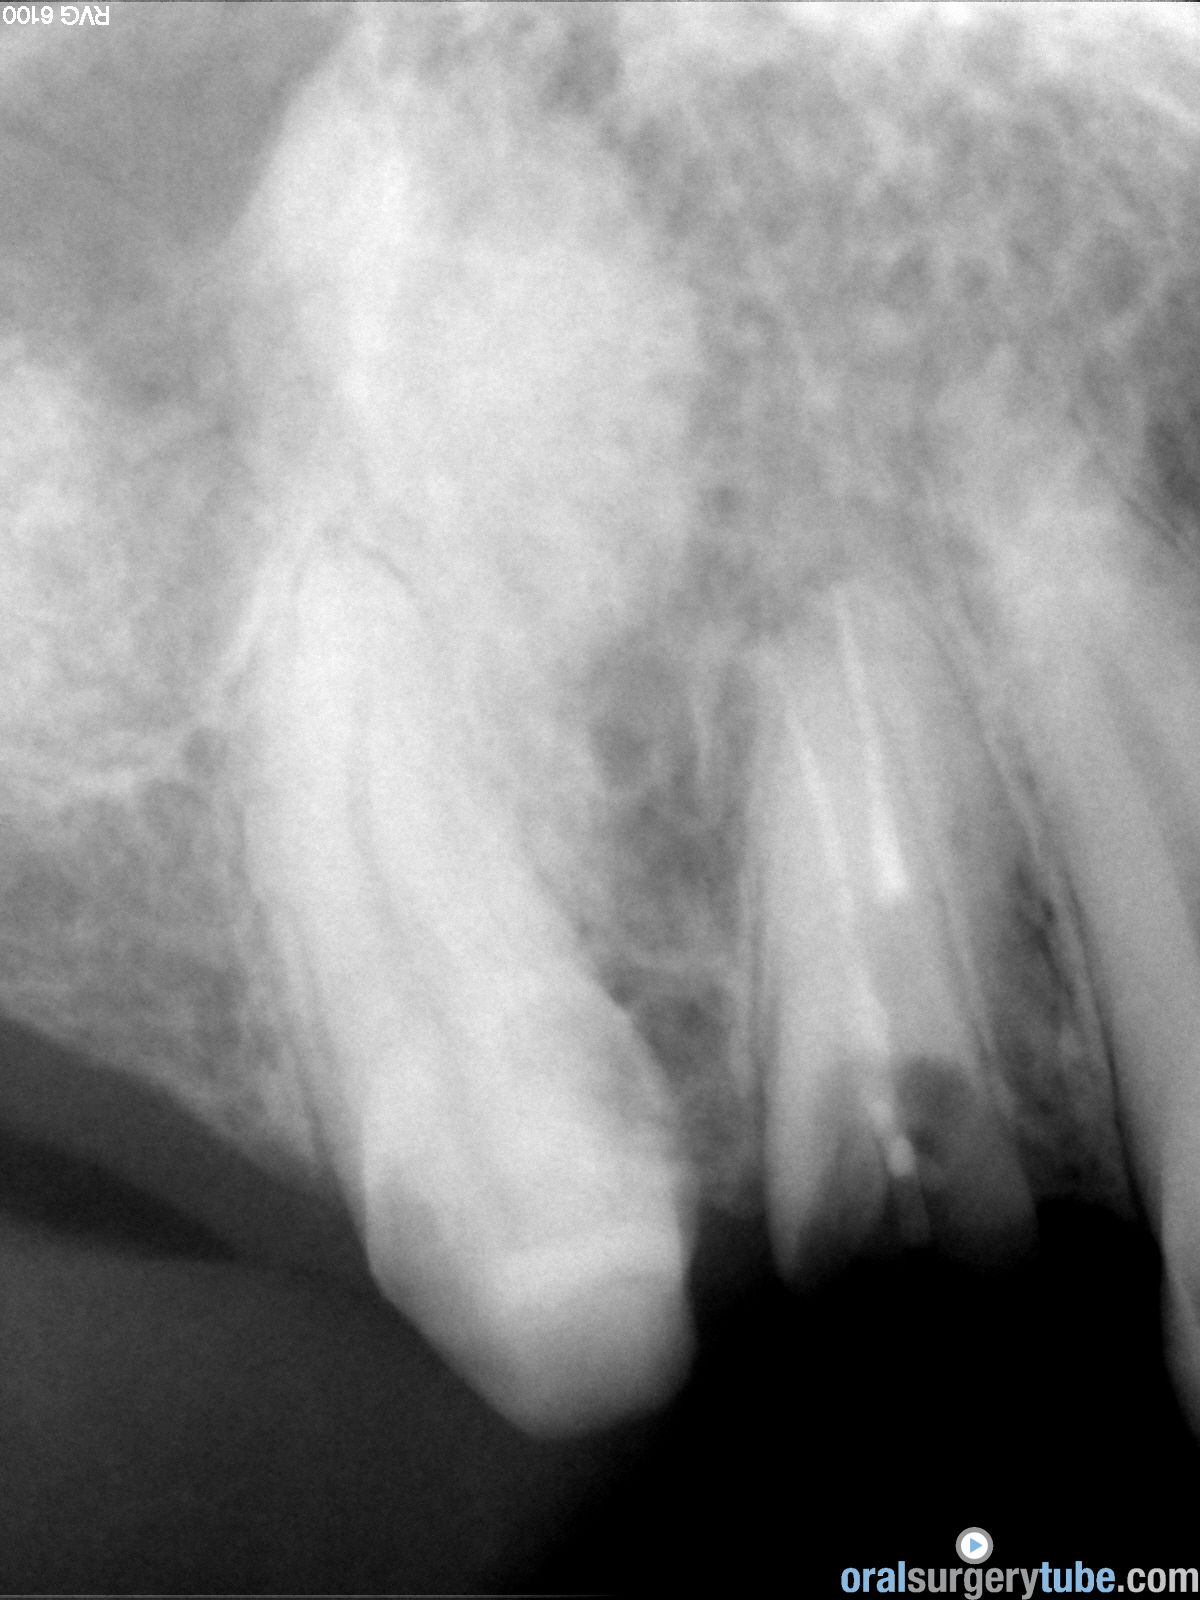

Respondo a Hernán Rescala: Antes que nada, darte las gracias por tu comentario. Este paciente llevaba dos coronas ferulizadas 1-4; 1-5 cuando le vimos en 2014. En aquel momento, no se hizo ningún tratamiento, y fue una pena. La pieza 16, por la que ha venido toda esta historia era recuperable. Quizás no supimos convencerle de intervenir de inmediato, de lo cual me culpo. Subo panorámica de 2014. Volvió en 2018 con las coronas caídas y el pilar 1-4 totalmente destruido. La pieza 1-5 era vital y colocamos un provisional, el cual descementó varias veces. La 1-4 decidimos mantenerla para hacer un implante cuando colocáramos los demás. El dia de la cirugía del seno, vino con el provisional roto, pero al no tener mucha sensibilidad en la pieza, intervinimos y lo dejamos tal cual. Después de tu observación volvimos a valorar esta pieza el viernes 13 con un test pulpar y Rx, que subo. La pieza sigue vital, con pruebas frio, calor y eléctrica(12 en escala 1-100). Subo TAC previo

Continúo con el seguimiento que vamos dando a este paciente: Visitado el miércoles 11.07.2018. Hay ausencia total de sintmatología. Retiramos el drenaje, hacemos Prueba de Valsalva positiva, pero sale aire y un poco de sangre. Dejamos cicatrizar por segunda intención. Pedimos continuar la medicación antibiótica y solicitamos un TAC. El seno maxilar está ocupado como vemos en la imagen, pero el biomaterial está contenido en la zona injertada: no existe ningún gránulo de xenoinjerto dentro del seno. La apófisis mastoidea está aireada.